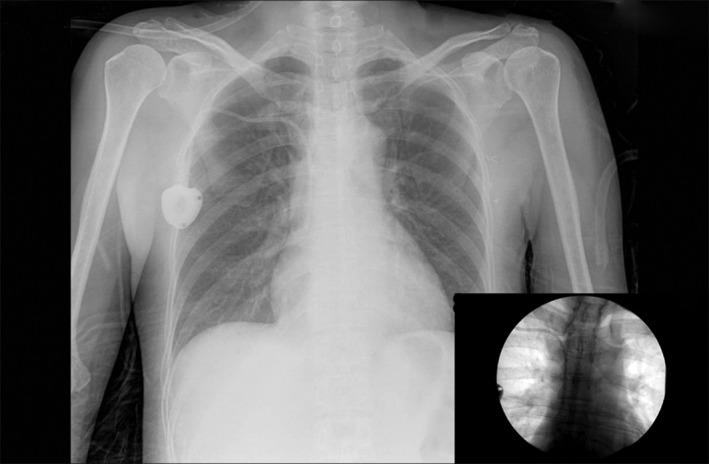

The extravasation of cytotoxic agents into subcutaneous tissue is a serious complication of chemotherapy. Unfortunately, if such extravasation occurs into the pleural space, limited data is available to guide appropriate management. We present the first report in the literature of video-assisted thoracoscopy combined with a topoisomerase II inhibitor and iron chelator, dexrazoxane, in the successful management of this complication.

细胞毒药物渗出到皮下组织是化疗的严重并发症。不幸的是,如果这种外渗发生在胸膜腔,可用的数据有限,无法指导适当的治疗。我们首次在文献中报告了使用胸腔镜联合拓扑异构酶 II 抑制剂和铁螯合剂右雷佐生成功治疗这种并发症。